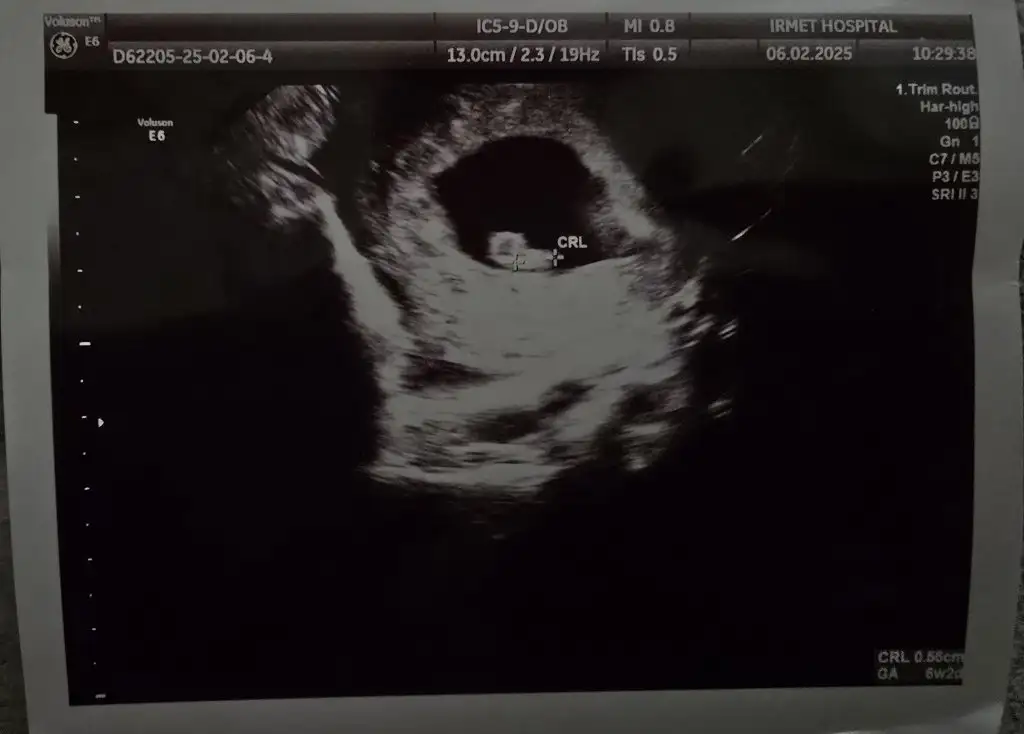

Merhaba kızlar bugün gittim karından gözükmedi

Vajinadan baktık anca öyle göründü

6+2 yim Lioo Lioo

Benim vajinal olma sebebi büyük bir kistim var bebeği kapatıyordu o yüzden

kalp atışını da duyduk şükür 🥰 kan tahlilleri istedi rutin o kadar şuan